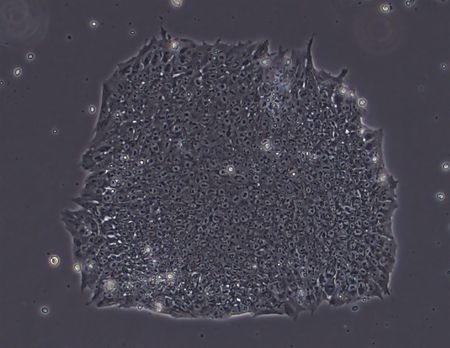

Kioto, 22 de mayo (Jiji Press)— Investigadores de la Universidad de Kioto anunciaron el martes que han logrado producir células madre embrionarias que podrían ser utilizadas en la medicina regenerativa por primera vez en Japón.

Las células madre embrionarias tienen el potencial de transformarse en distintos tipos de tejido al igual que las células madre pluripotentes inducidas, o células iPS.